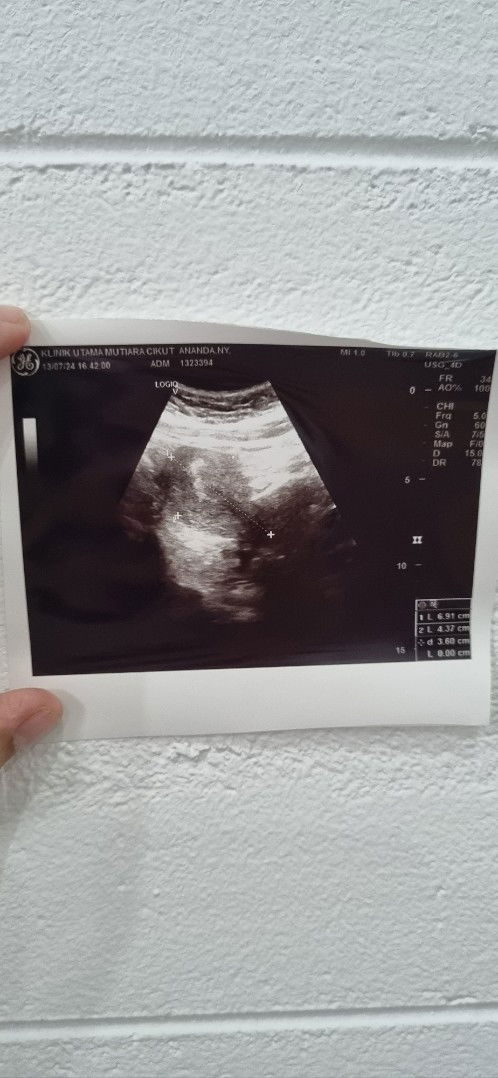

Bunda, mau tanya aku kan kemarin ini periksa, karna baru telat 5 hari, testpack positif garis jelas dua2nya dihitung dari HPHT usia di 5 minggu, tapi saat USG yg kelihatan baru penebalan dinding rahimnya aja, katanya kantungnya lagi bersiap. awalnya berangkat ke dokter udah optimis hamil, tapi pas pulang mendadak hopeless karna bingung sebenernya aku hamil atau engga yaa?#Sharing_dong_Bund #SeriusTanya #ingintahu #firstmom #pertamapositif